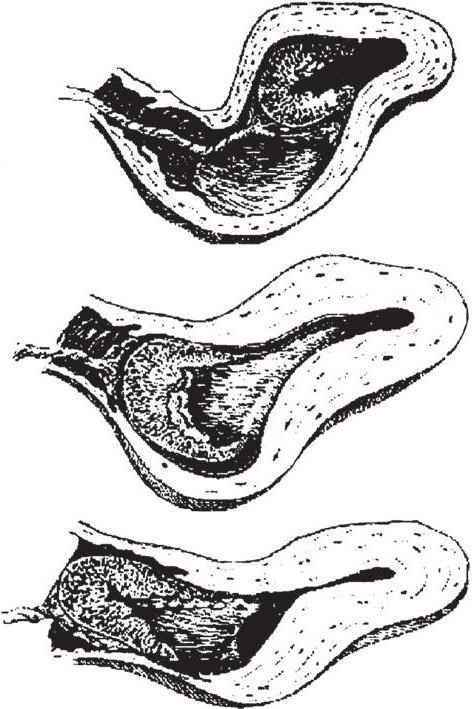

Медицинская визуализация: Признак Кюстнера-Чукалова